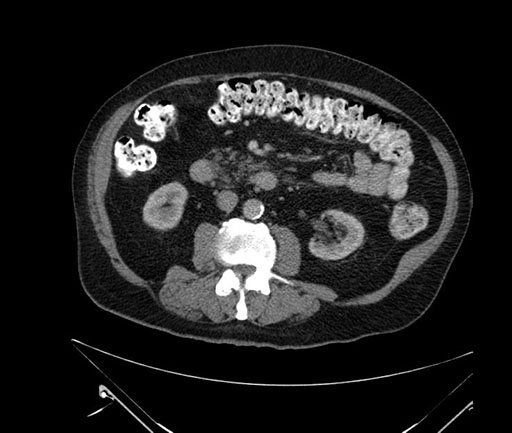

Axial - stented